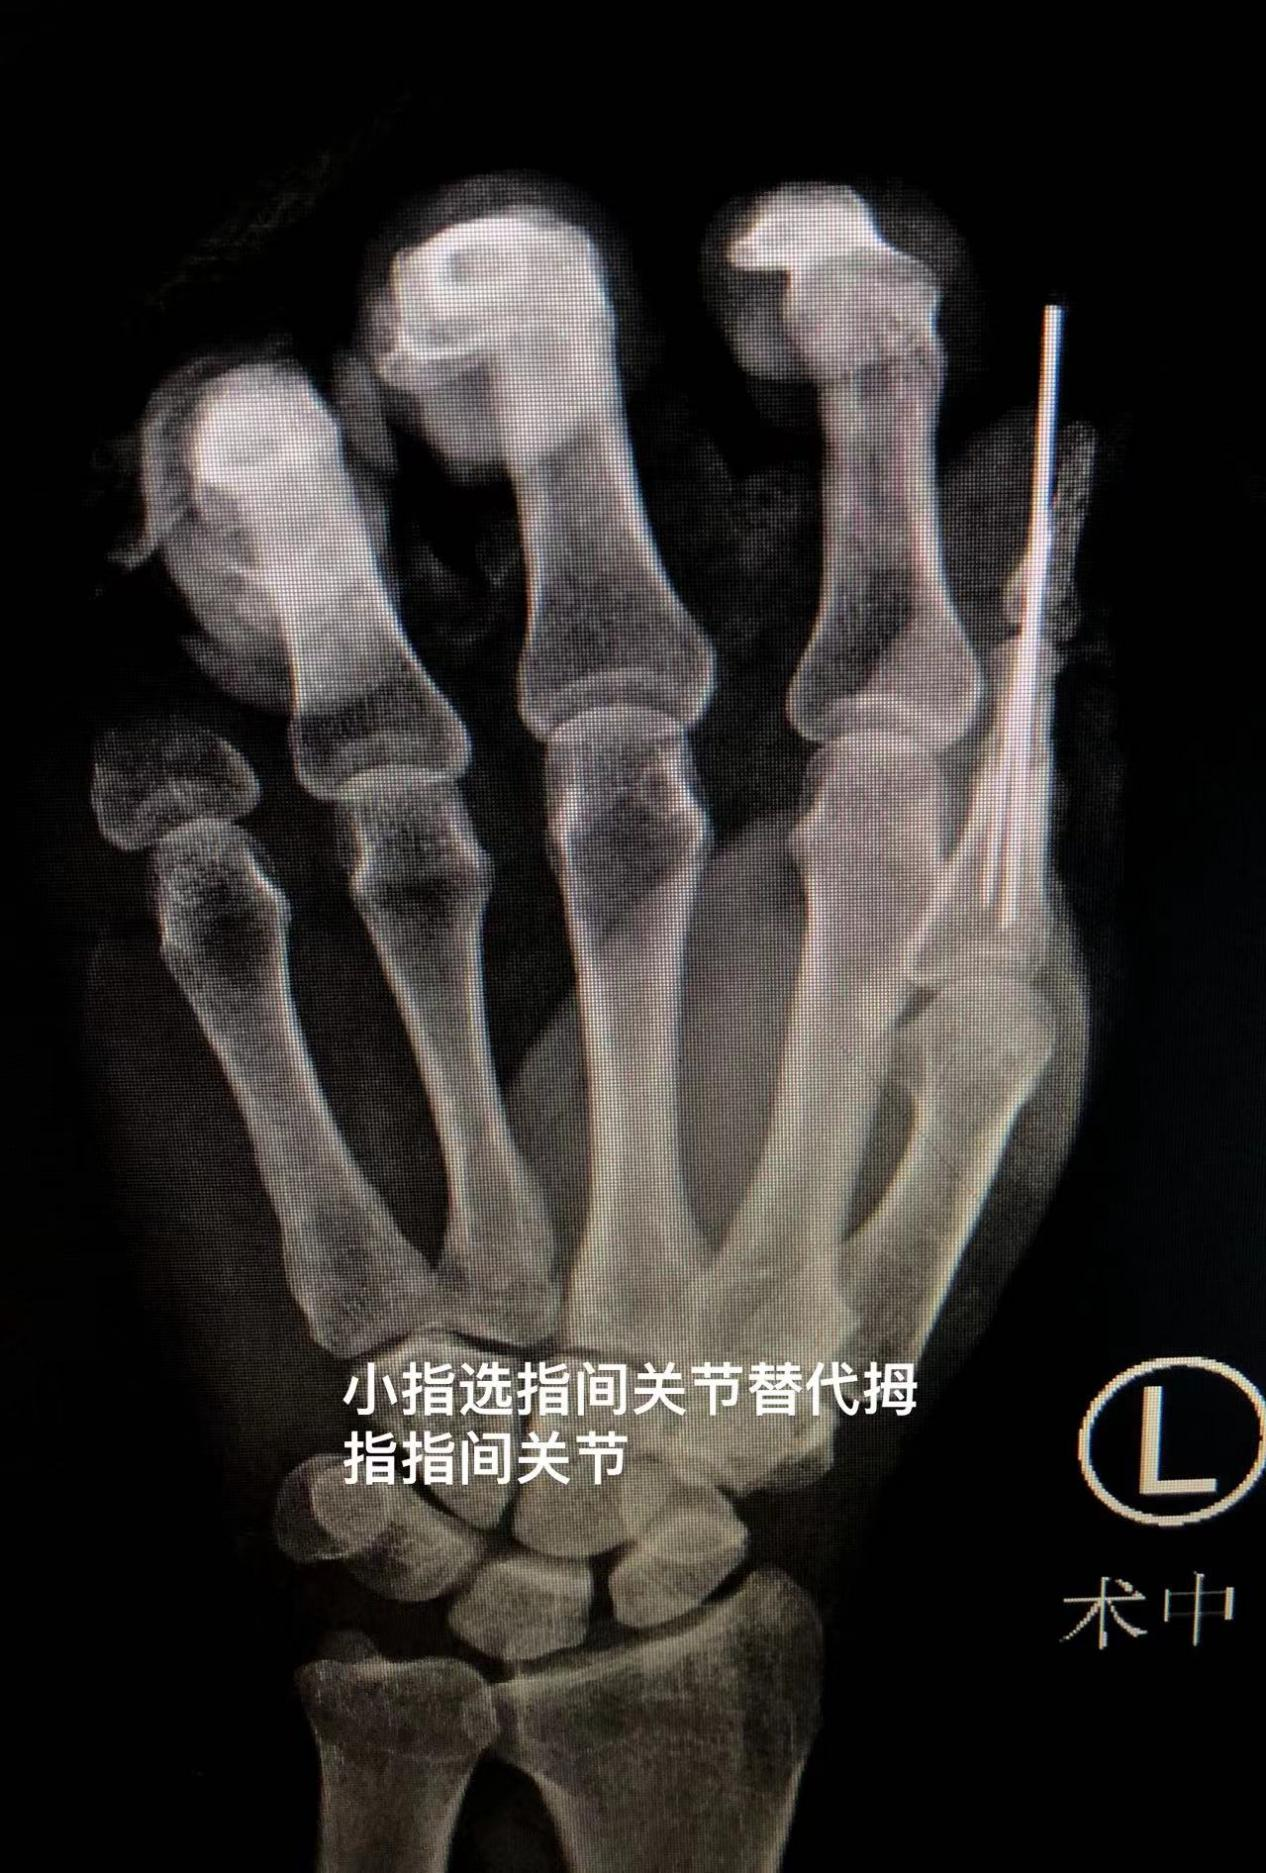

此时,黎章灿手术团队经过激烈的术前讨论,提出了一种更加完美的方案:将离断的小指异位再植到拇指上,并对小指的残端进行修整。这样可以用小指的远指间关节来替代拇指的指间关节,尽最大可能和程度地恢复患手的功能。

经过4个小时的奋战,手术团队成功地将刘师傅的左小指再植到拇指上,并完成了左示中环指血管神经肌腱断端的修复。术后,在医护人员的严密监护下,刘师傅已经顺利度过了断肢再植的危险期,目前恢复状况良好。